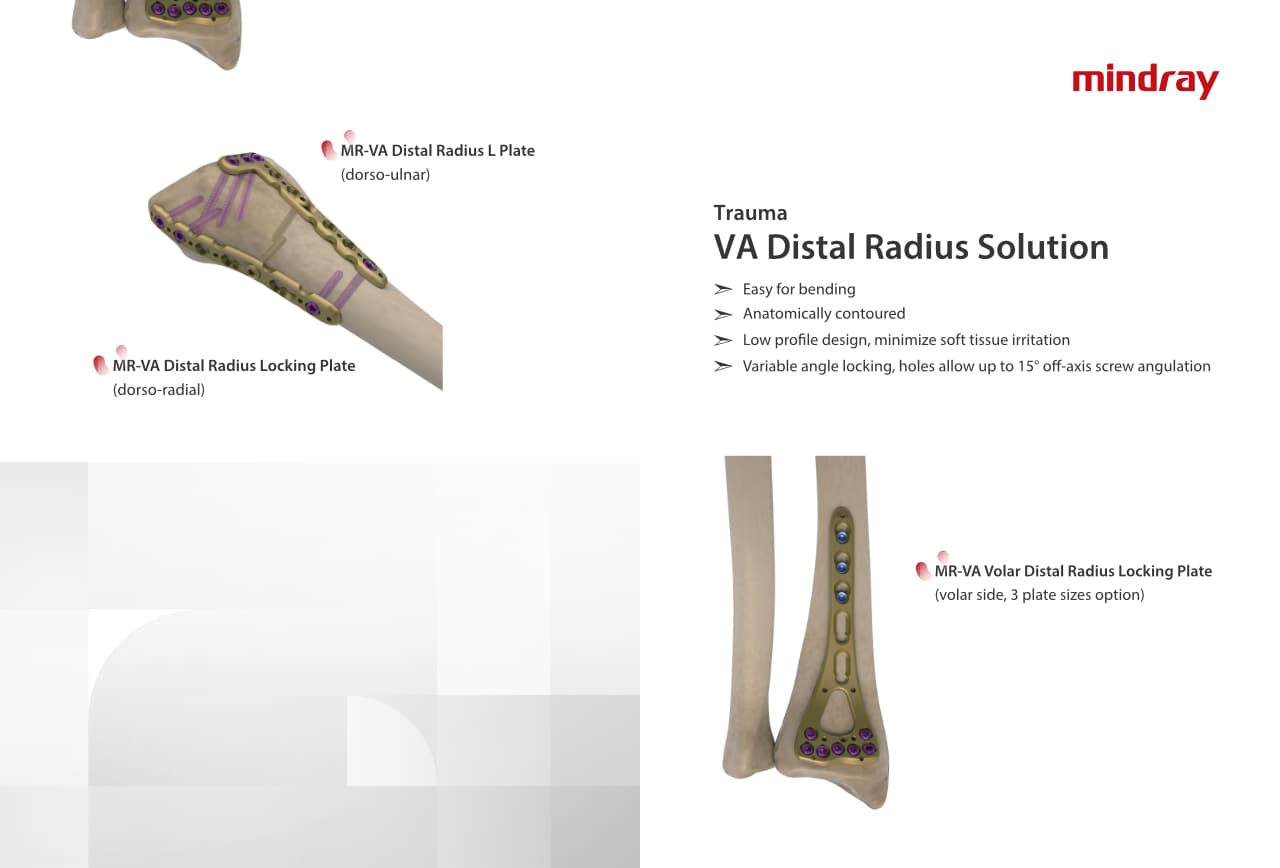

Trauma